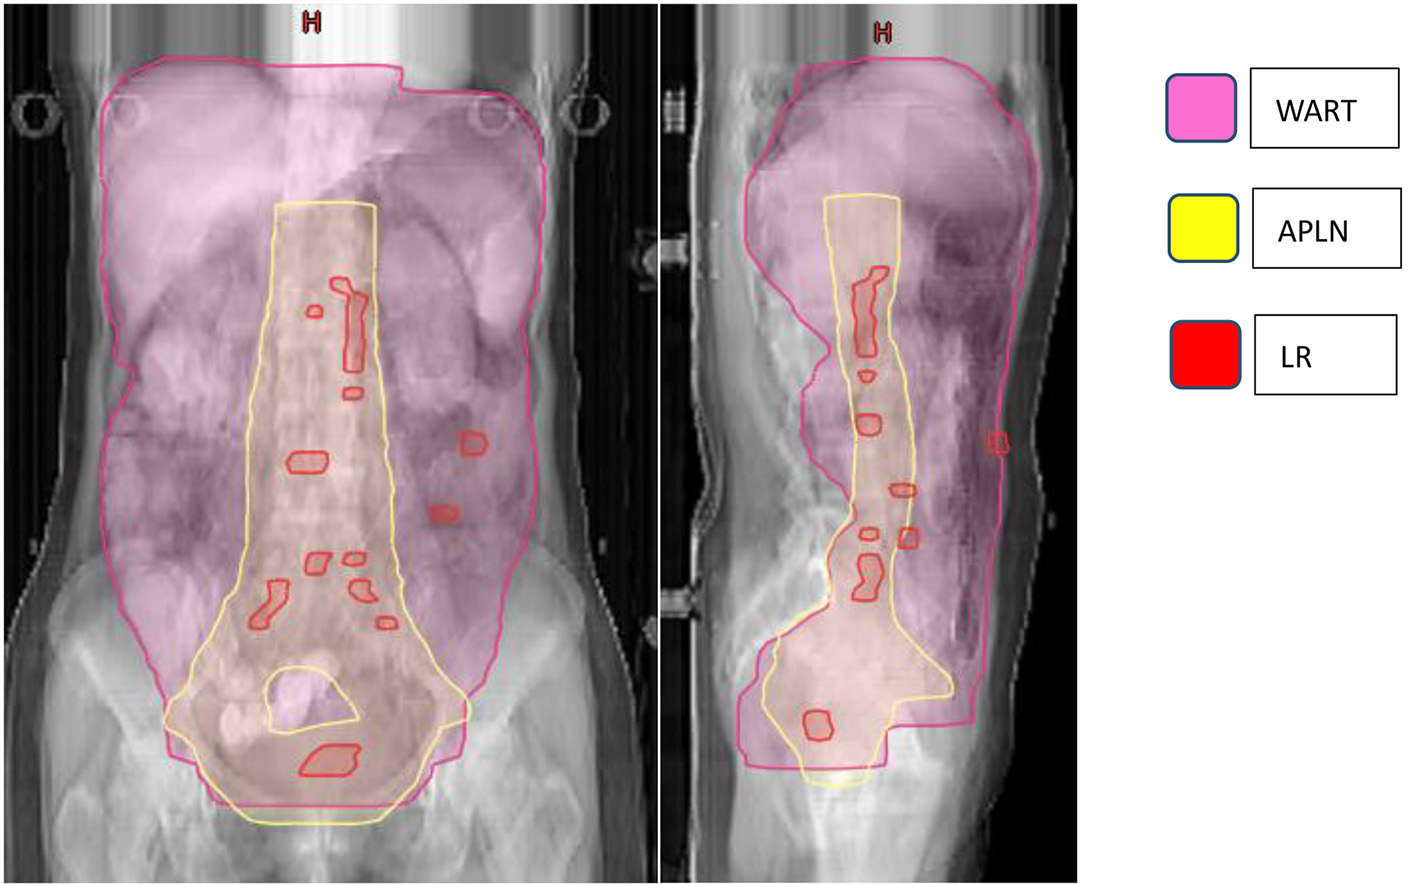

A total of 52 patients presented with disease failure, including 20 cases of local recurrence, 50 cases of distant metastasis, and 18 cases of combined local recurrence and distant metastasis at the same time. Among the 20 patients with local recurrence: seven patients with recurrence in the para-aortic lymph nodes, six patients with recurrence in the pelvic lymph node area, two patients with recurrence in the vaginal stump, three patients with recurrence in the mesenteric area, and one patient each with recurrence in the inguinal area and abdominal wall. Among the 50 patients with distant metastases: nine cases of lymph node metastases in the clavicular region, eight cases of liver metastases, five cases of lung metastases, four cases of mediastinal metastases, three cases of brain metastases, two cases of bone metastases, and 19 cases of other sites (breast, axilla, etc.), as detailed in Table 2 and Figure 3.

![]() Click for large image | Figure 3. Failure map for patients treated with APLN. *The yellow line represents the area of APLN (vaginal stump and pelvic lymphatic drainage area (common iliac, external iliac, internal iliac, closed foramen region, and anterior sacral region), abdominal aorta PALN (upper border at the level of T12). The pink line represents the radiation area of WART. The red rods represent LR. The failure map shows 20 patients with LR: 13 para-aortic or pelvic lymph nodes, two vaginal stump, three mesenteric area, and one inguinal and one abdominal wall, and three with recurrence between the area of WART and APLN. APLN: abdominopelvic lymphatic drainage area irradiation; PLAN: para-aortic lymphatic drainage area; WART: whole abdominal radiotherapy; LR: local recurrence. |

The local failure mode in patients with locally advanced ovarian cancer is mostly the lymphatic drainage area near blood vessels [23, 24], and our center innovatively applied preventive irradiation of the abdominopelvic lymphatic drainage area instead of total abdominopelvic irradiation, which greatly reduced the normal tissue exposure and increased the target area irradiation dose to 45 - 50 Gy. The mean follow-up time was 64.10 months (5.5 - 113.2 months), 5-year OS was 61.5%, 5-year DFS was 40.9%, and median DFS was 40.8 months after a course of adjuvant chemotherapy with the application of IMRT technique for radiotherapy to the abdominopelvic lymphatic drainage area, with improved median survival and OS in patients with advanced ovarian cancer compared to the SEER database (40,692 patients in the 1995 - 2007 database), and Baldwin et al reported relative 5-year survival rates of 36% and 17% for patients with FIGO stage III and IV epithelial ovarian cancer, respectively [14], compared with a median DFS of 27.6 months and 5-year OS of 33.0% in the OVAR-IMRT-01 study, both of which were greatly improved. Patients who underwent APLN were followed up, with distant metastasis as the main failure mode and local recurrence in the irradiated field in fewer patients, accounting for only 2/99 cases, confirming the relevance of performing abdominopelvic lymphatic drainage area prophylactic radiotherapy in patients with locally advanced ovarian cancer. Moreover, the associated toxic side effects were small due to the reduction of irradiation field, with acute side effects: grade 3 hematological toxicity in 67/99 cases, and for late toxic side effects, a total of 10 patients showed grade 3 gastrointestinal disorders, one patient died due to the repeated three times operations. Comparing with the reported literature above, the severe advanced toxic side effects were small.